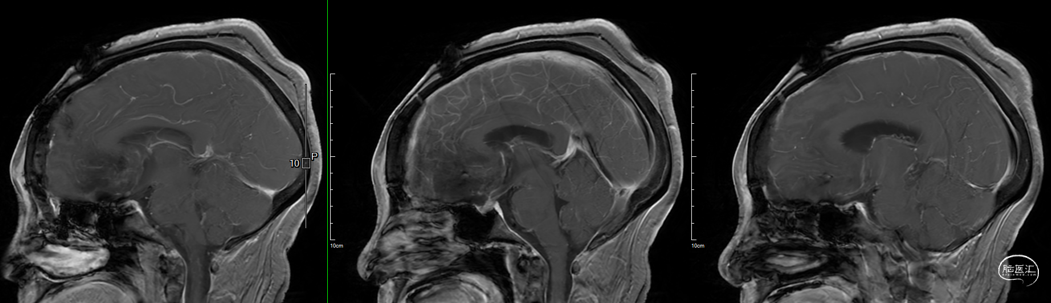

术后影像学

![]()

头部MRI提示:影像学全切,脑积水得到明显好转,实性部分未见显影,垂体组织保留良好。